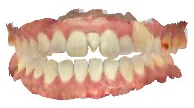

患者さんの年齢 20代 女性 症状 八重歯がコンプレックス、白い歯を入れたい 治療内容 セラミック治療 費用 費用150万(税抜) 治療期間・回数 治療期間1ヶ月・通院回数3回 メリット 治療期間・回数が少ない デメリット・リスク 術後知覚過敏が起こる事ある - セラミック治療

before

after